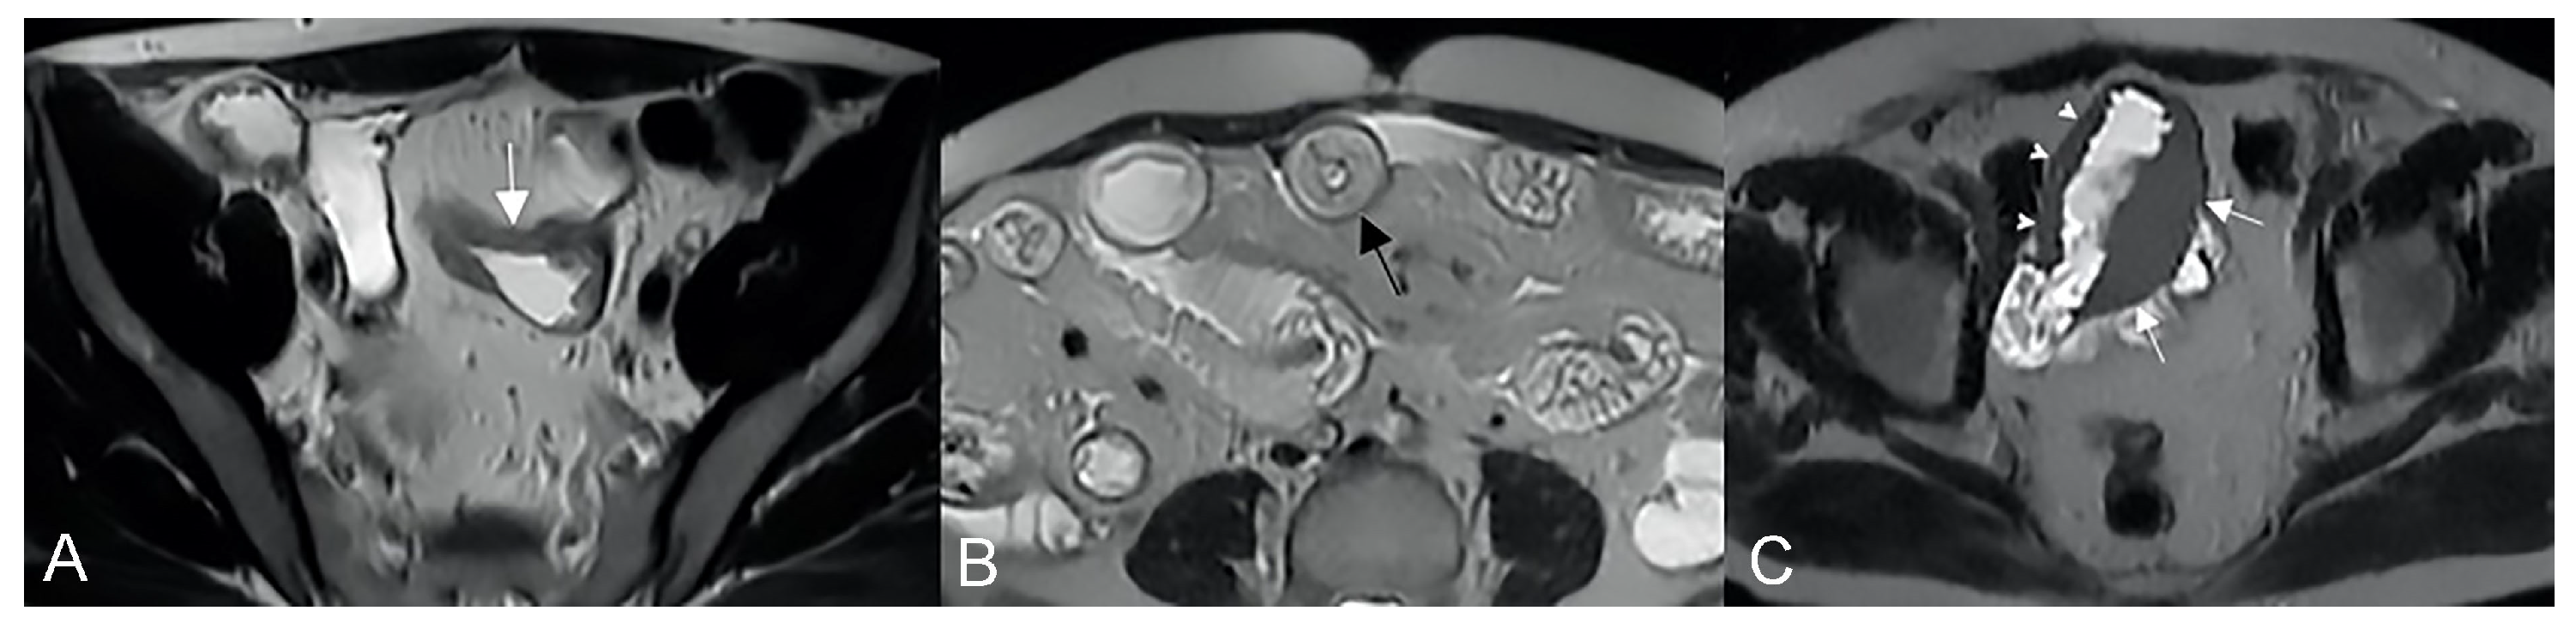

Figure 16.

Degree of wall thickening and type of involvement along bowel circumference. (A) Axial T2-weighted image shows mild thickening (<1 cm) of an ileal loop in the pelvis (arrow). (B) Axial T2-weighted image shows moderate symmetric thickening (>1 cm and <2 cm) of a small bowel loop (black arrow), supported by edema of the submucosal layer. (C) Axial T2-weighted image shows marked asymmetric thickening (>2 cm) of an ileal loop in the pelvis (arrows); the other side of the bowel wall is less thick (arrowheads).